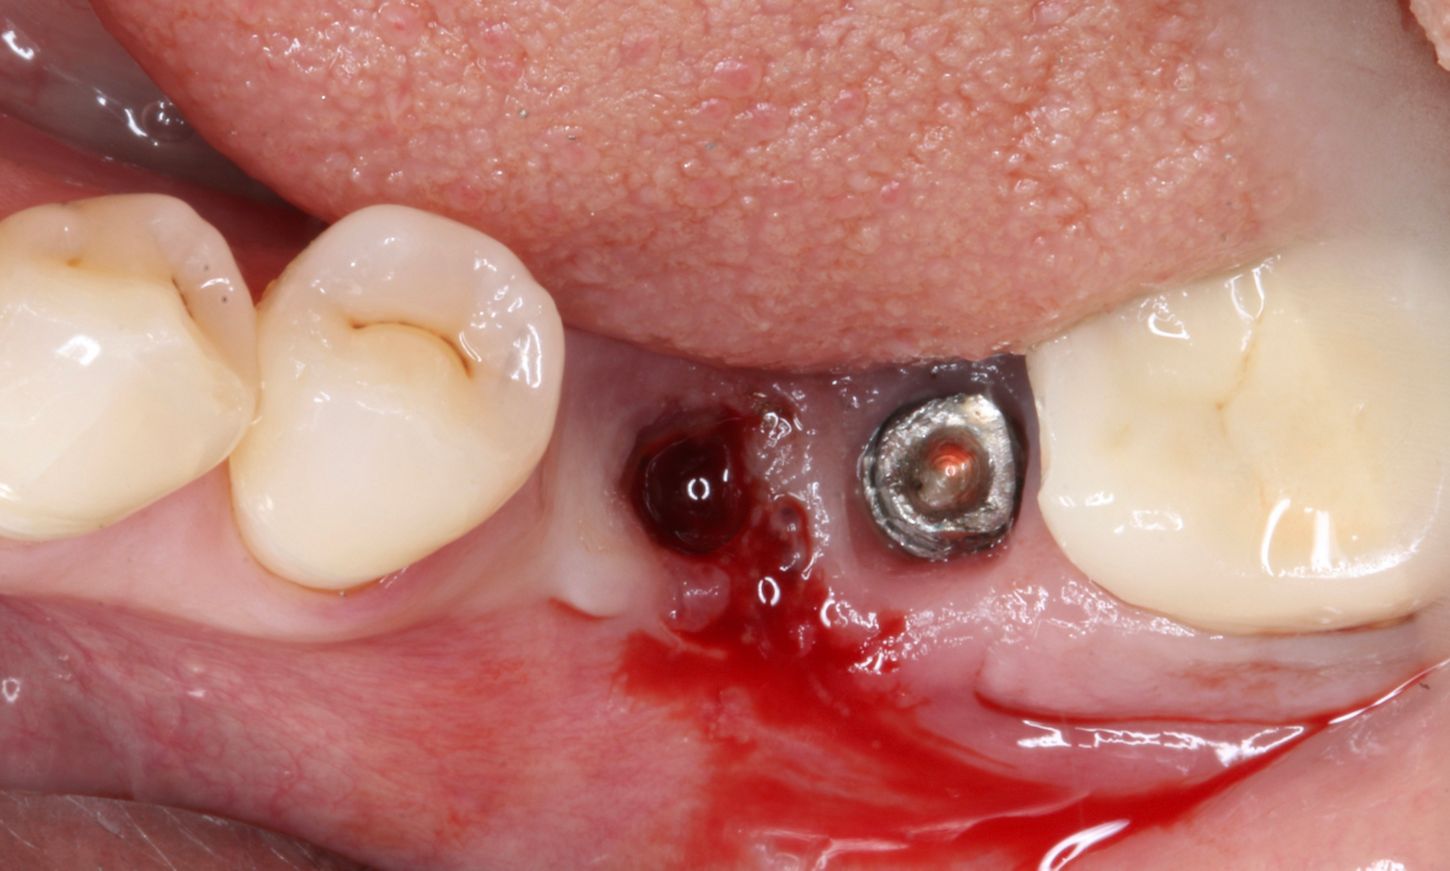

The implant cleaning and disinfection were done with CHX 0.12 % and the GalvoSurge®. Implant disinfection was performed using GalvoSurge®, applying only gentle pressure to the implant being treated. In this 2-minute process, hydrogen ions interact with captured electrons to produce hydrogen bubbles that lift the biofilm off the implant surface (Fig. 6). Additionally, regenerative therapy was performed through GBR. Autogenous bone chips, combined with bone harvested from the tuber, were placed into the defect as grafts. These materials helped in bone augmentation and covered the exposed implant threads, thereby enhancing the healing and re-osseointegration at the implant site (Figs. 7-9).

Tooth #38 was extracted. Closure caps were placed, and the Straumann® Membrane Flex, a minimally-crosslinked porcine peritoneum collagen membrane, was fixed in place with pins. This protects the graft area from unwanted soft tissue infiltration during the healing phase (Figs. 10-12).